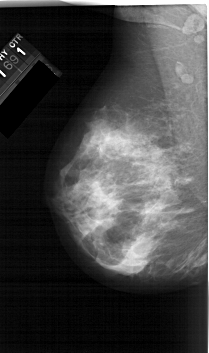

A_1566_1.LEFT_CC

LEFT_CC LINES 6181 PIXELS_PER_LINE 3451 BITS_PER_PIXEL 12 RESOLUTION 43.5 NON_OVERLAY